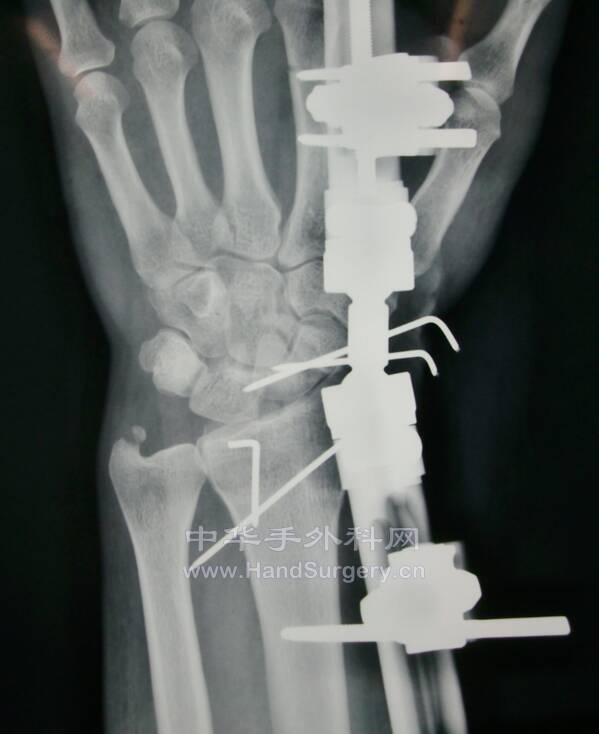

桡骨远端骨折,远端粉碎或太短,不能接受钢板远端钉排

克氏针+外固定支架是绝佳选择

这里就是其中一个典型病例

桡骨远端骨折C3型合并舟骨骨折